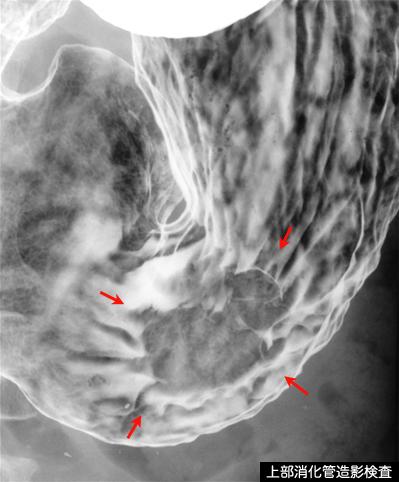

Criteria of Hist.ClassificationMalignant epithelial tumor/Adenocarcinoma

LocationStomach/Angle

Technique, MethodX-ray

Macroscopic TypesType 1 Protuberant (polypoed) type/

Size35 - 40

Depth of Tumor Invasionsubserosa (subadventitia)